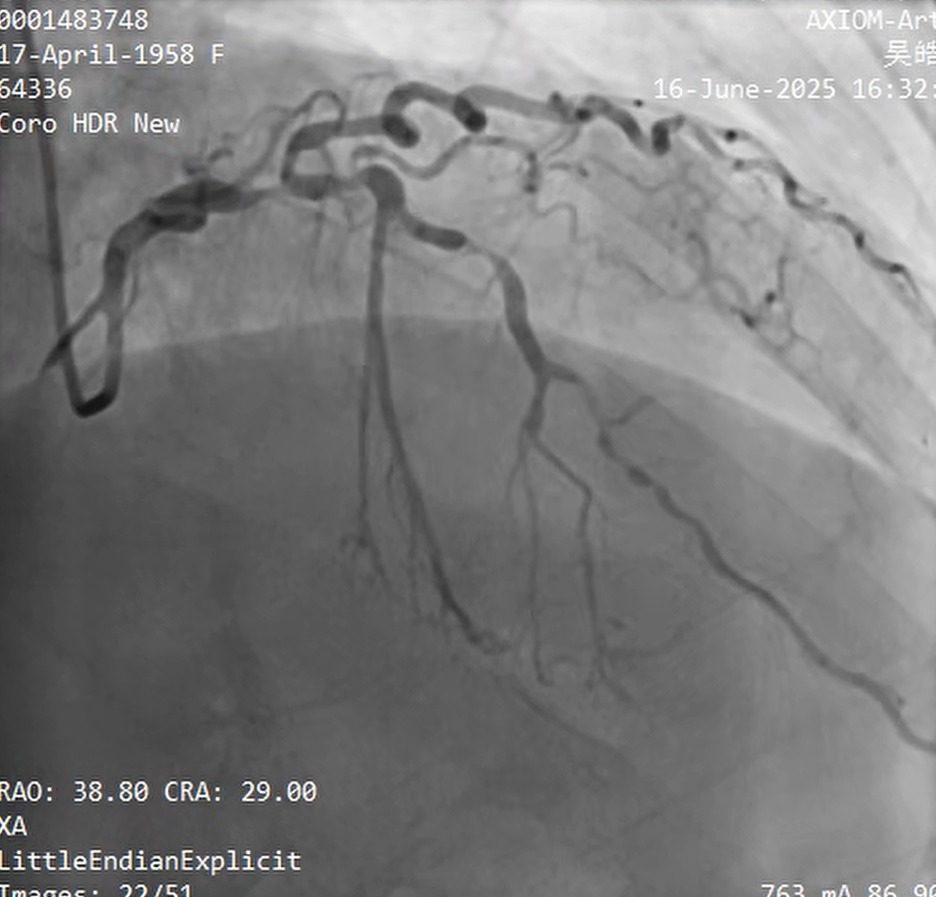

Relevant Catheterization Findings

30% stenosis in LMT; 100% stenosis in LCX£»99% stenosis with calcification in the LAD£»99% stenosis in the RCA¡£